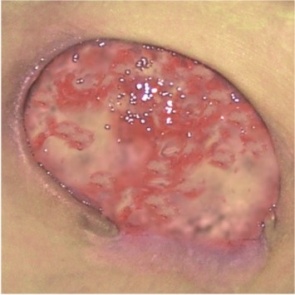

RANA „CZERWONA” – TKANKA ZIARNINUJĄCA

CHARAKTERYSTYKA RANY:

- rana w kolorze jasnoczerwonym, wilgotna

- powierzchnia rany nierówna

- tkanka delikatna, wrażliwa na ból, podatna na zakażenia

ZALECANE OPATRUNKI:

- Medisorb A, Medisorb P lub Medisorb P PLUS – rany z wysokim lub średnim poziomem wysięku

- Medisorb H – rany ze średnim i niskim poziomem wysięku

- Medisorb G – rany zakażone z niskim poziomem wysięku (sprzyja oczyszczaniu rany przez wiązanie uprzednio uwodnionej martwej tkanki wraz z drobnoustrojami, które ją kolonizują)

- Medisorb A – w przypadku ran zakażonych z wysokim poziomem wysięku